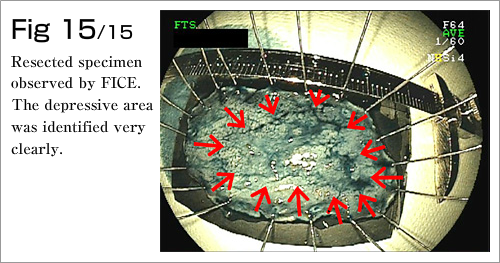

The procedure is done in several steps. First, the margins of the lesion are marked by electrocautery, and then a submucosal injection is used to lift the lesion (Diagram 4-8). After which, a circumferential incision into the submucosa is made around the lesion (Diagram 9). Finally, the lesion is dissected from underlying deep layers of GI tract wall with electrocautery knife and removed (Diagram 10-13). The lesion, mainly existing in the mucosal layer (1st layer), can be completely excised along with the submucosa (2nd layer)(Diagram 14-15).